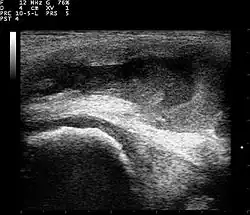

Ultrasound

Ultrasound imaging may be used by your doctor in their office as a diagnostic tool to better visualize the effusion and its size. This can also be an effective tool to guide treatment such as a joint aspiration.[10]